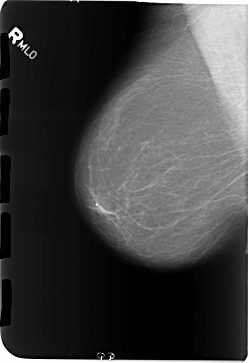

B_3171_1.RIGHT_MLO

RIGHT_MLO LINES 5800 PIXELS_PER_LINE 3984 BITS_PER_PIXEL 12 RESOLUTION 50 NON_OVERLAY